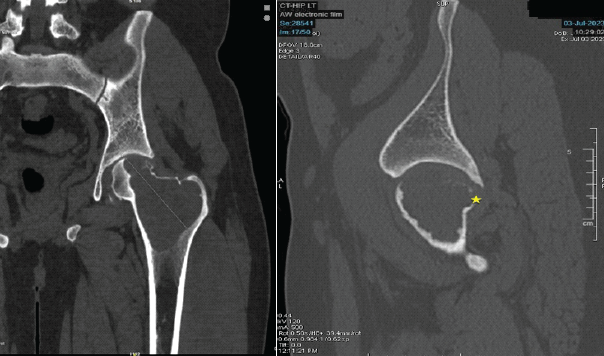

A 29-year-old man from South India presented with pain in the left hip for the past 1 year, with increased intensity for the past 5 months. Pain was dull aching, continuous without any diurnal variation. He also has difficulty walking for the past 5 months. On examination, there was tenderness around the left trochanteric region and around the joint line. His movements of the hips were restricted and extremely painful. He was primarily wheelchair-bound with limited mobility. His X-ray and computed tomography (CT) scan showed an eccentric expansile lytic lesion measuring approximately 7.7 × 5.7 × 3.2 cm in the proximal left femur involving the superolateral portion of the femoral head, neck of femur, greater trochanter and intertrochanteric region (H1 and H2 area and minimal involvement of H3 area as per the International Society of Limb Salvage) with no matrix mineralization [Fig. 1 and 2].

Figure 2: Computed tomography scan shows extent of involvement with breach in the superior cortex portion of femoral head and neck. These are pre-operative computed tomography scan images taken before the surgical procedure, at the time of presentation. These sections confirm the bony involvement and extent of the lytic lesion, essential for pre-operative planning.

Cortical dehiscence was noted in the superolateral aspect of the femoral head and also in the anterior and posterior cortices of the neck of the femur with mild effusion in the hip joint. His magnetic resonance imaging reports also confirmed similar findings with narrow zones of transition without acetabular involvement. His routine blood chemistry and chest CT scan were normal. He underwent ultrasound-guided fine-needle aspiration cytology, which confirmed the diagnosis of GCT. The case was discussed in tumor board meeting. Since there was an extensive involvement of the femoral head and neck, and trochanteric area with a cortical break in the femoral head and neck, he was planned for near total excision of the tumor, EC of the remaining lesion from the lesser and greater trochanteric area, and THR, along with systemic therapy using injection denosumab.